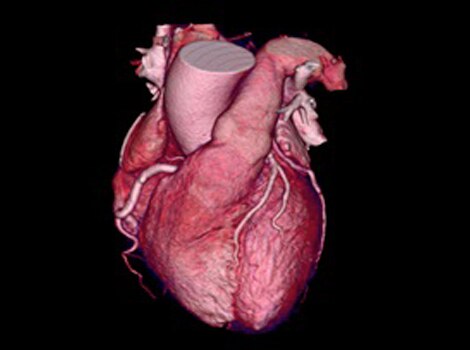

3D Heart

Visualize the anatomical structures and vascularity of the heart with a bright blood, 3D sequence.

Visualize the anatomical structures and vascularity of the heart with a bright blood, 3D sequence. Read More